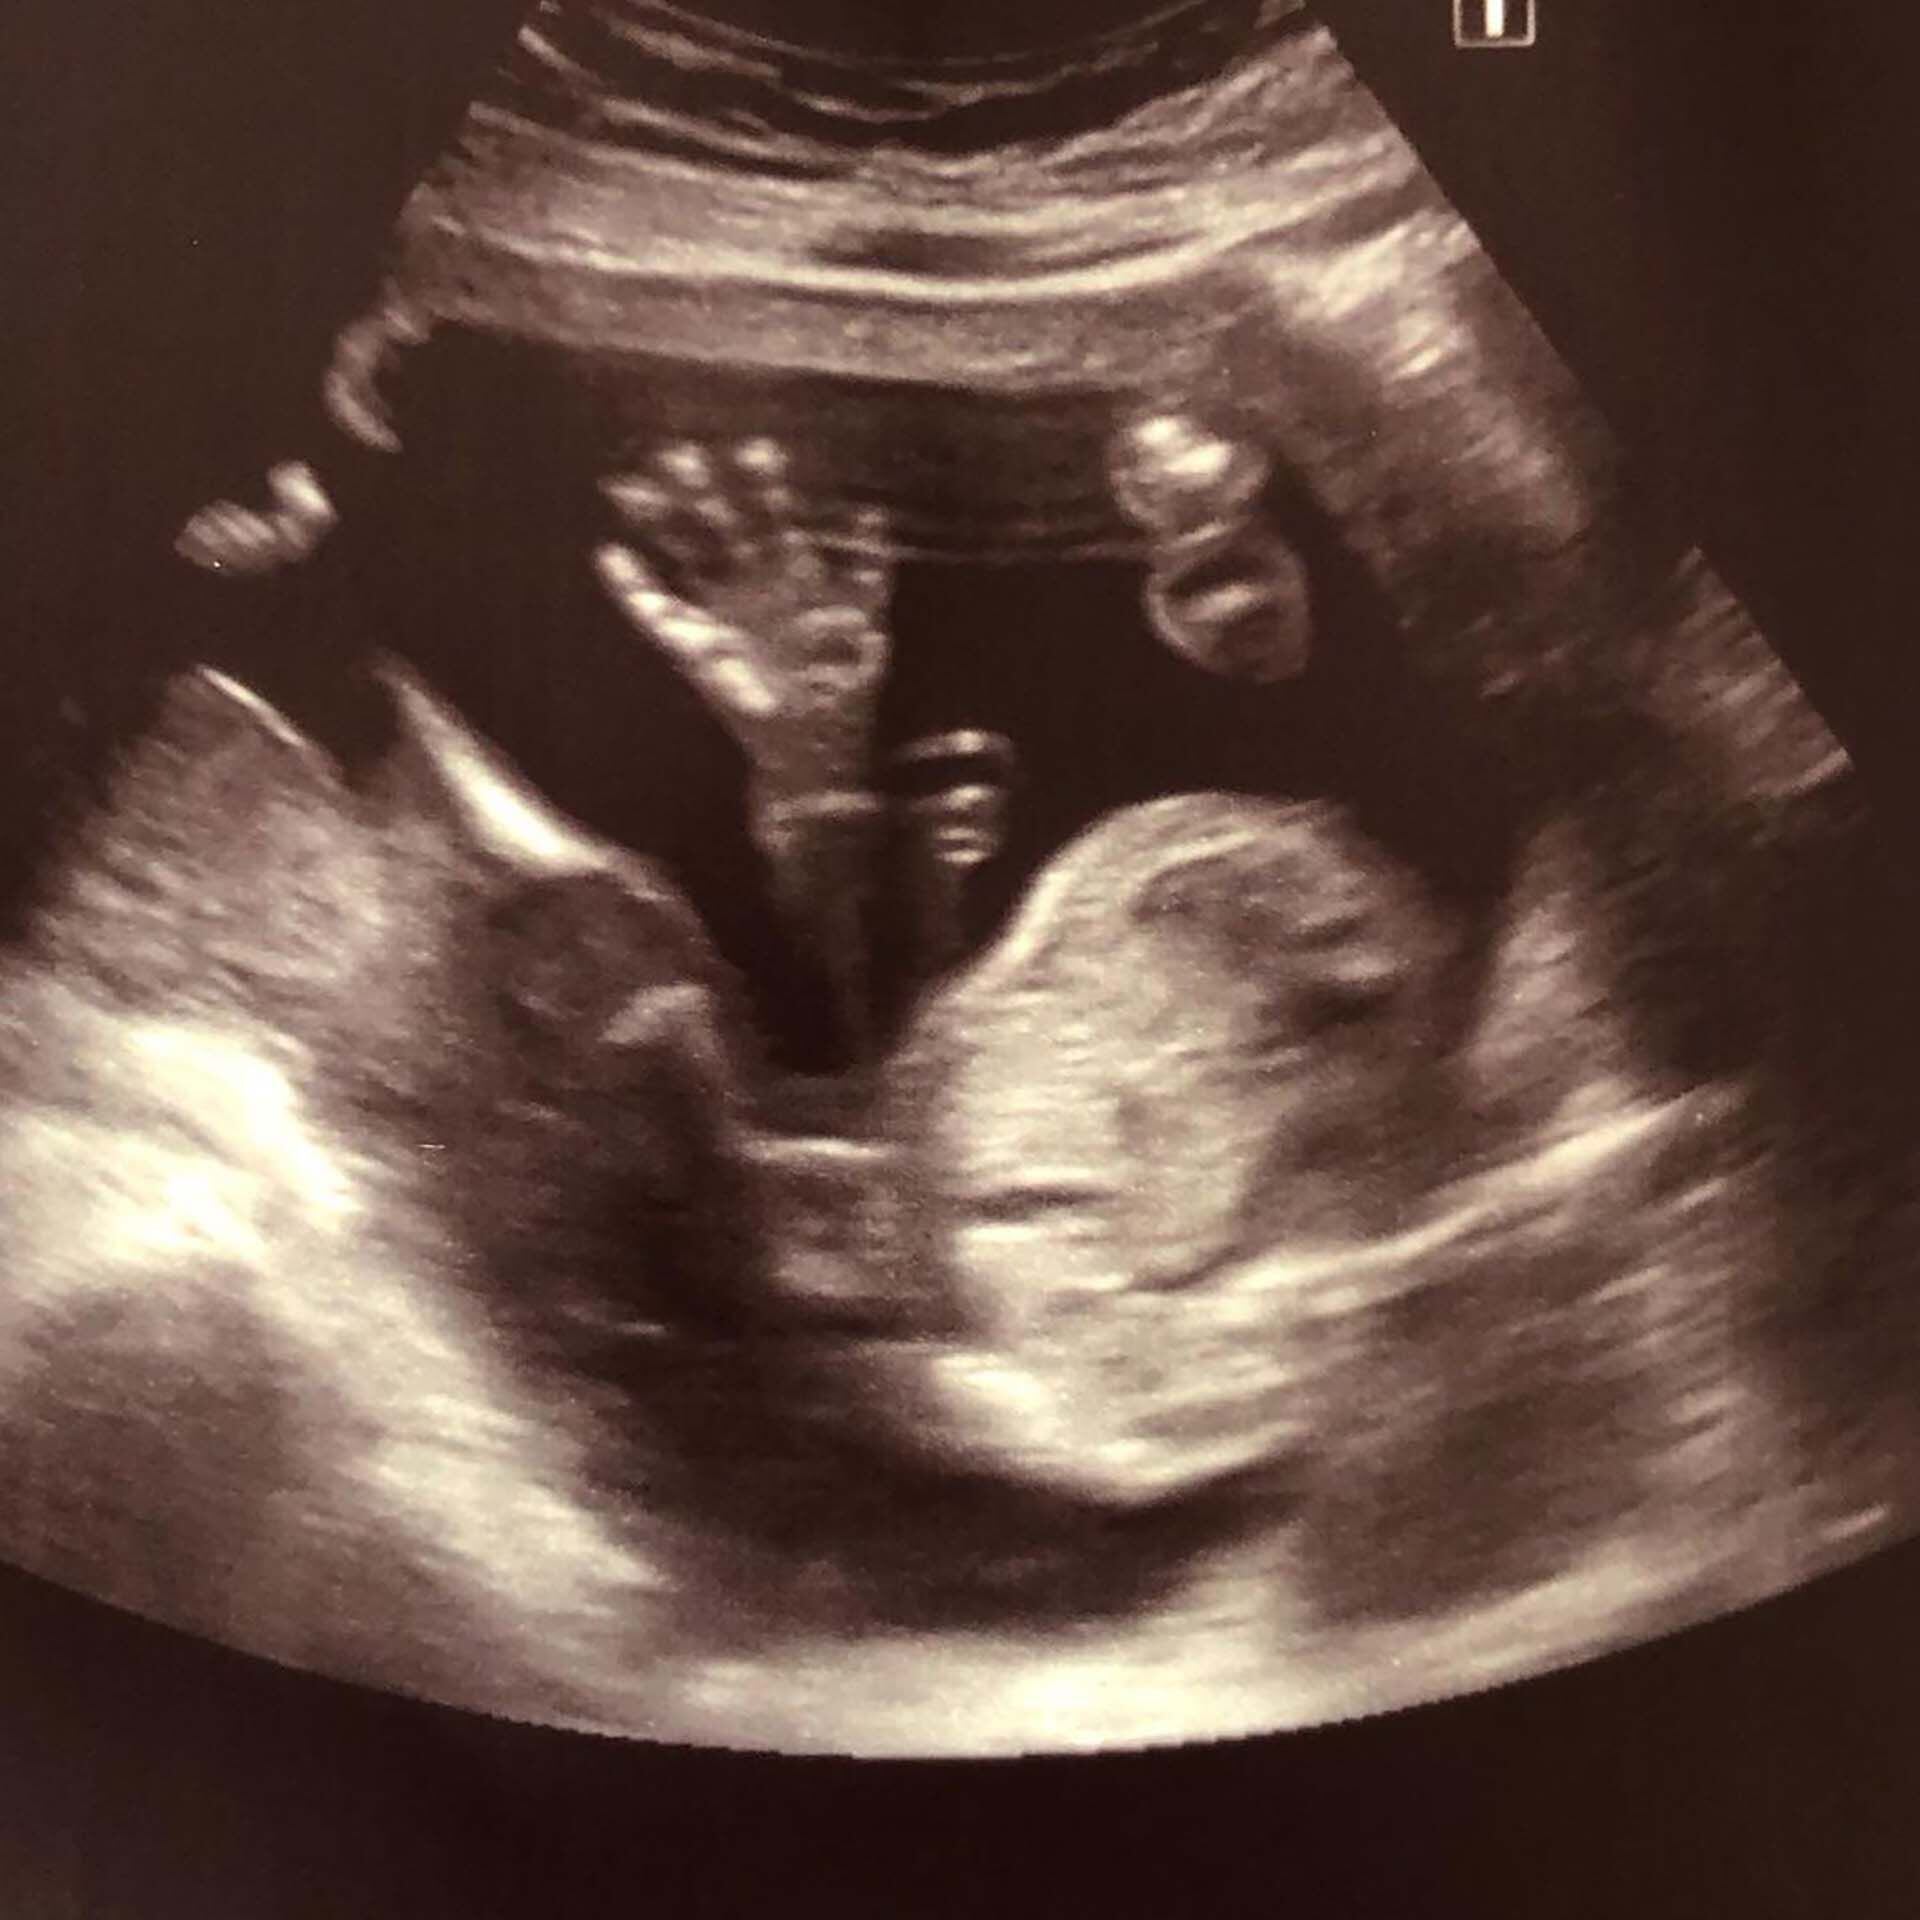

La mano de Antonia

“No lo pude compartir mucho, algunos amigos ni siquiera llegaron a verme embarazada. De hecho tuve que ir a las ecografías sola”, recuerda. Pero Antonia crecía lo más bien, Johanna se sentía perfecta, así que el resto era una anécdota.